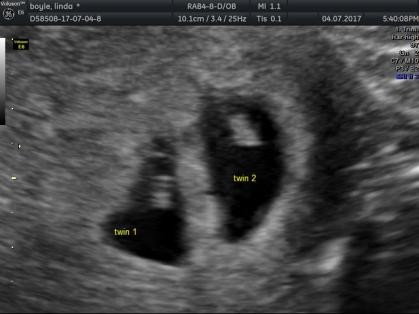

However, some women do need a scan before 12 weeks . Between 8 - 12 weeks of pregnancy is a good time for a dating scan . A 2-D image of a baby at about 8-9 weeks . Small arms are becoming visible, sticking out slightly in the middle of the baby . The wavy line near the bottom of the image measures the heartbeat which in this baby is

A dating scan might be recommended before 12 weeks to confirm your due date if you are unsure of your last menstrual period or your date of conception . The scan is optional and not everyone will have it . You can discuss whether you want or need a dating scan with your doctor or midwife . A dating scan is usually done to check how many weeks' pregnant you are, but can be done for other reasons, such as if you have had bleeding during your pregnancy or you have had previous miscarriages .

The common first step will be a dating scan between 7-10 weeks as we like to check your baby before 10 weeks . Why scan at 7 weeks ? An ultrasound is performed at this stage of pregnancy to confirm your due date, confirm if you are having singles, twins or more and to visualise your baby's heart beating . Before 7 weeks it may be too early to acquire this information . How is the scan performed?